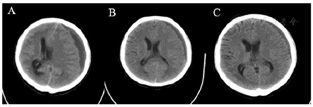

患者骨髓涂片、免疫分型、染色体、BCR-ABL基因定量和ABL突变结果明确诊断为慢性髓系白血病急淋变,ABL F317L、Y253H突变。头颅CT显示头颅硬膜下血肿,大脑镰疝,胸部CT示肺部感染,胸腔积液。

3.影像学结果:(1)头颅CT结果(图2)。(2)胸部CT结果(图3)。(3)心电图和心超未见明显异常。